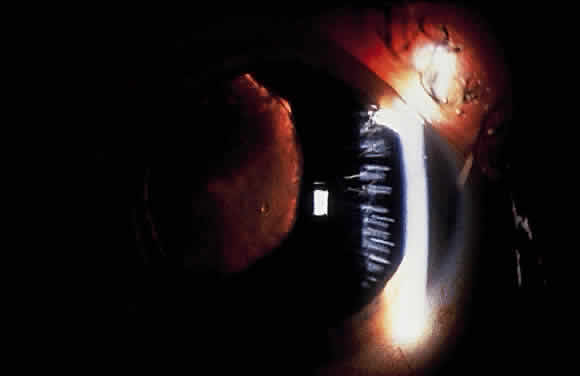

Lens

Deposition of exfoliative material on the anterior lens surface is the most commonly recognized feature of XFS and usually is best appreciated after pupillary dilation.43 A bull's-eye pattern generally is seen in which a translucent central zone and a granular peripheral zone of deposition are separated by an intermediate clear zone (Fig. 1). The translucent central zone of exfoliative material varies in diameter and may exhibit curled edges. In approximately 20% of patients with exfoliation, the central zone may be absent.38 The intermediate clear zone presumably results from lens contact with movement of the iris. The granular peripheral zone, which may be subtle but invariably is present in XFS, generally exhibits a well-delineated inner border and often shows numerous radial striations (Fig. 2). Occasionally, a bridge of exfoliative material may cross the clear zone to join the central zone and the granular peripheral zone.38,44

Fig. 1. Typical bull's-eye pattern of exfoliation on lens surface showing separation of central and peripheral zones of deposition by intermediate clear zone.

Fig. 2. Granular peripheral zone with well-defined inner border and numerous radial striations.